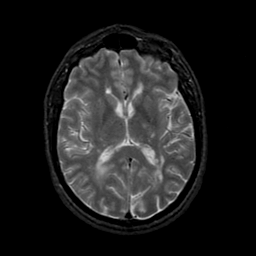

MR Study #21, November 3, 1991 -- Slice #27